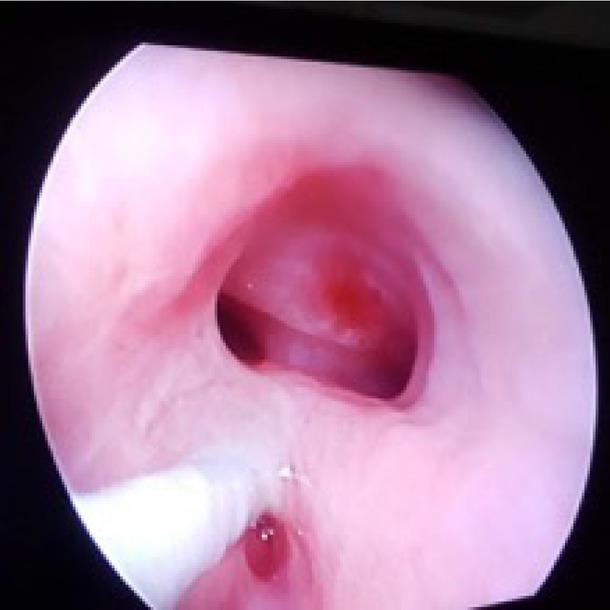

Figure 3